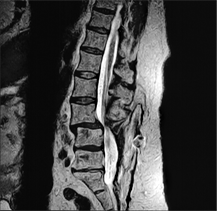

Above, are lumbar spine images of a patient who had undergone back surgery but continued to experience pain. The MRI image on the left was acquired with the patient lying down. It shows a normal alignment of the vertebrae. However, when the patient was scanned in an upright position on the same MRI scanner on the same day (image on the right), a dramatic spinal instability was clearly revealed. This problem, visible only when the patient was scanned upright, would have gone undiagnosed on a conventional, lie-down MRI scanner.